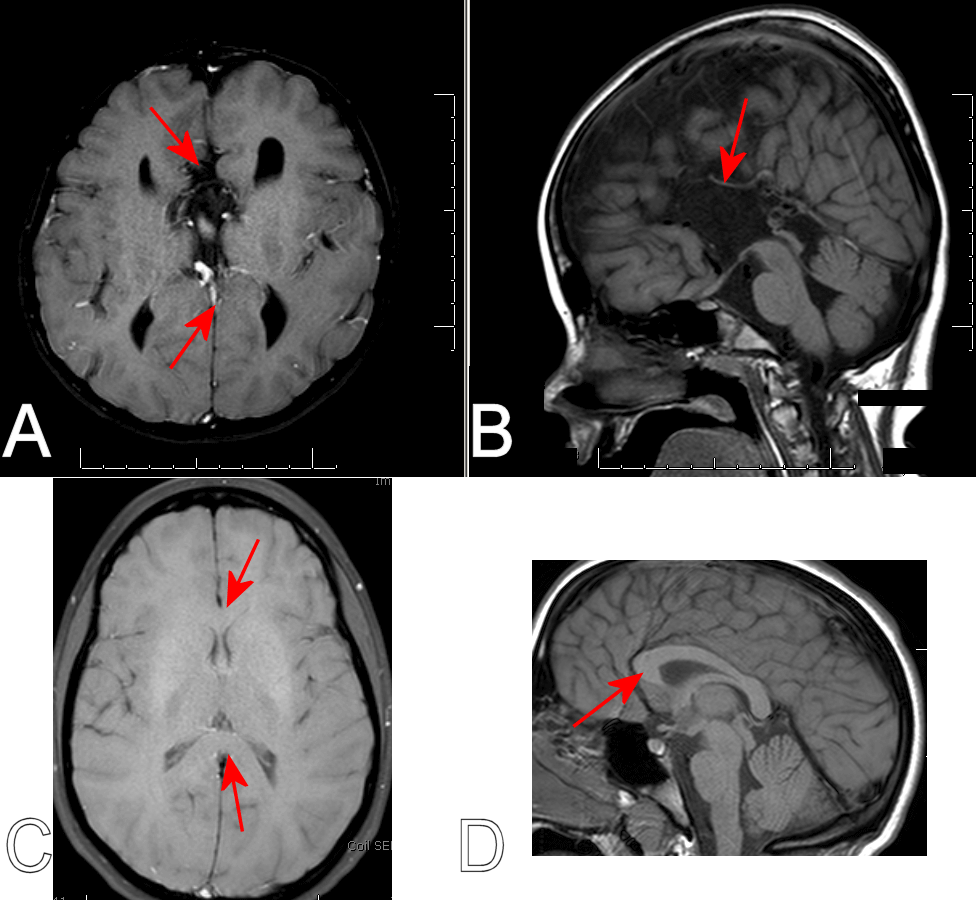

Diagnosis: Corpus Callosum Agenesis

Figure 1: A: Axial T1 image showing no intra-hemispheric connections. B. A mid-sagittal cut showing no evidence of a corpus callosum. Arrows in A and B show where the corpus callosum would normally be found. C and D are shown for comparison, and demonstrate a thick corpus callosum connecting the two hemispheres.

There are some cases in which a very thin corpus callosum exists but is difficult to visualize. In these cases, the gyrus immediately adjacent to the thin corpus callosum would run rostro-caudally. In cases that truly have no corpus, like that shown above, the gyri tend to run perpendicular to where the corpus callosum would normally sit.